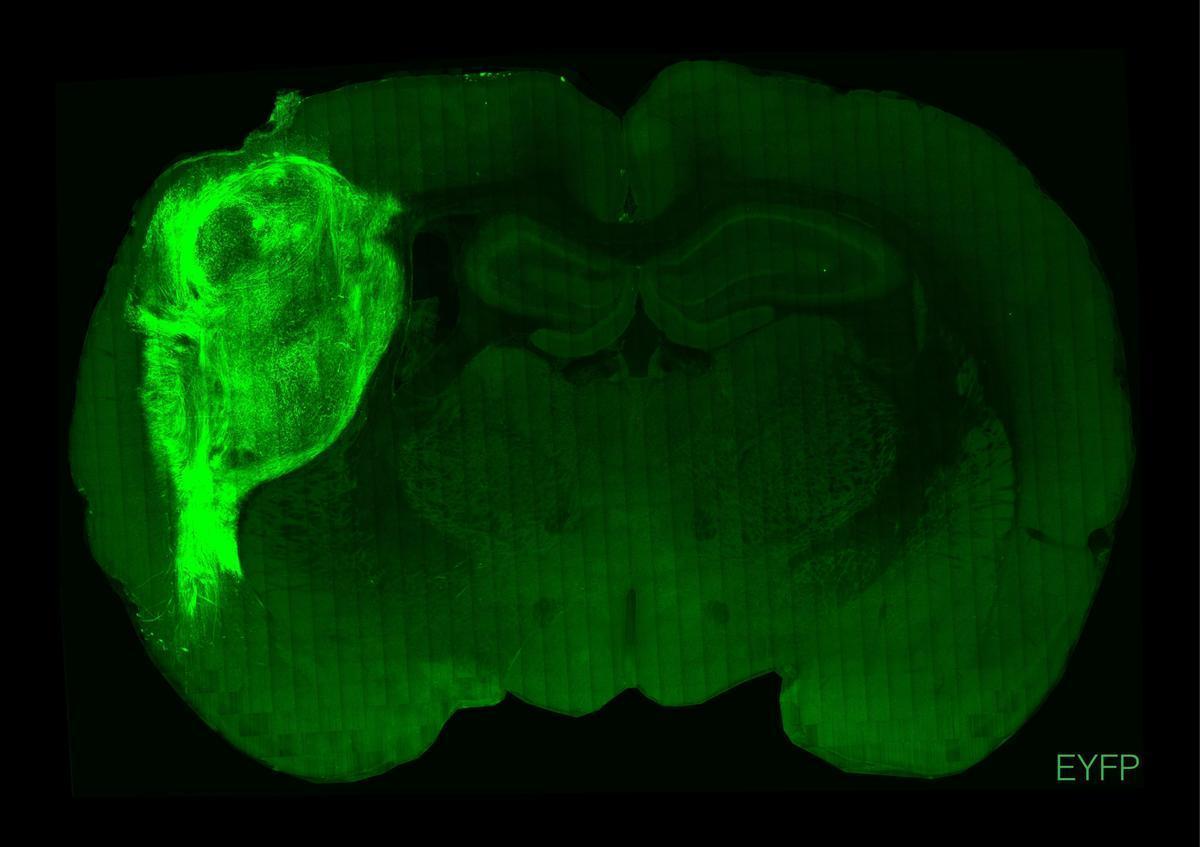

Imagen del ’minicerebro’ de células humanas transplantado a una rata. / Universidad de Stanford

La historia que leerán a continuación parece ciencia ficción pero no lo es. Es ciencia a secas. Un equipo de investigadores ha logrado cultivar unos minicerebros a partir de células madre humanas, trasplantar estos organoides en ratas recién nacidas y, a partir de ahí, modificar el comportamiento de estos animales. El logro, presentado este miércoles en la revista científica 'Nature', ha sido descrito como "un avance sin precedentes". Y como una herramienta que, en un futuro, podría mejorar el estudio de enfermedades neurológicas y psiquiátricas humanas.

No es la primera vez que se logra crear un minicerebro en un laboratorio. De hecho, ya hay varios grupos de investigación que han conseguido adentrarse en este fascinante hito. Pero, a diferencia de estudios anteriores, esta es la primera vez que se logra crear un órgano 'in vitro', trasplantarlo a un roedor, observar cómo los tejidos humanos se integran con los del animal, se establecen conexiones neuronales nuevas y se desarrollan células típicamente humanas en el cerebro de una rata. Nunca antes una investigación había conseguido una sucesión de éxitos así.

El logro, liderado por el investigador Sergiu Pașca de la Universidad de Stanford, se ha desarrollado de la siguiente manera. En primer lugar, los científicos cosecharon un 'minicerebro' a partir de células madre humanas. Una vez creado este órgano 'in vitro', lo trasplantaron a una rata recién nacida (de entre 3 y 7 días). Los tejidos humanos se insertaron justo en un momento en que el cerebro del animal estaba en periodo de desarrollo. De ahí que, según apuntan los autores de esta investigación, se lograra conectar las células humanas con las del roedor.

La investigación no solo ha conseguido trasplantar con éxito un minicerebro, sino que ha logrado influir en el comportamiento de los animales. Por un lado, gracias a una técnica conocida como optogenética, se modificaron genéticamente las neuronas para que cada vez que estuvieran expuestas a una luz activaran determinadas proteínas. Por otro lado, se entrenó a los roedores para obtener una recompensa cada vez que se acercaban al bebedero. A partir de ahí, los científicos observaron que cuando estimulaban las neuronas de los minicerebros artificiales, las ratas se dirigían directamente en búsqueda de la recompensa.